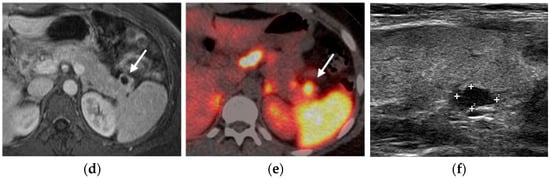

Ultrasound

Nuclear Medicine

Selective Venous Sampling